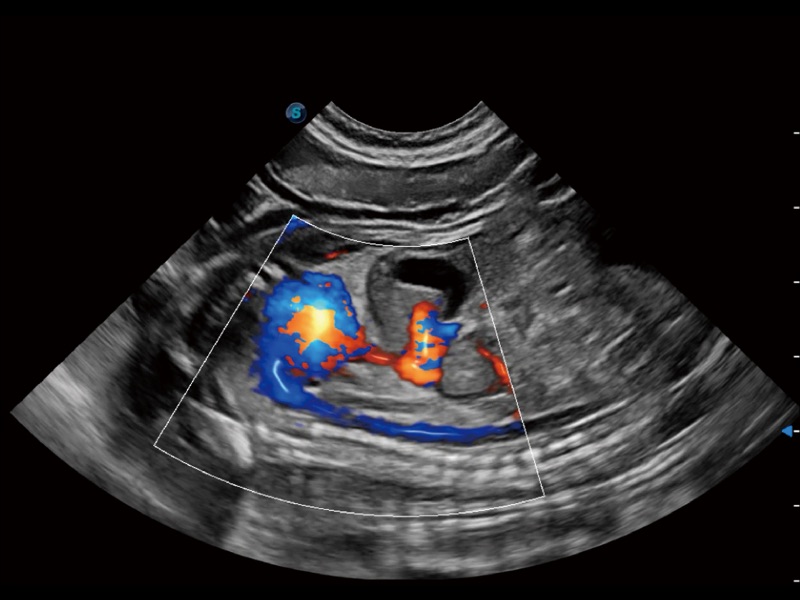

通过360度任意调节3条M型取样线,在同一心动周期上观察心脏不同位置的运动曲线,得到准确的心功能测量数据,有效评估心肌运动及左心室功能。